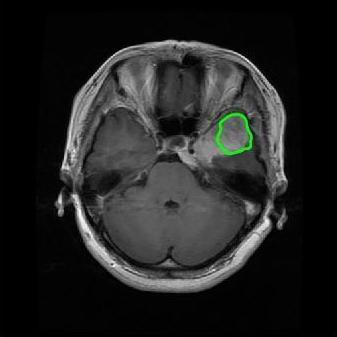

From the above discussions, we have discovered the significant potential of applying Retinex theory to image segmentation and explored its fundamental differences from traditional models. Traditional image segmentation models typically focus on the impact of intensity information on the segmentation results. Therefore, when faced with complex segmentation scenarios, the segmentation results are often affected by lighting, artifacts, and unclear boundaries in the image. As shown in Fig. 1, we present the results of the classical local model LIF [ZHANG20101199] for segmenting brain tumor images along with surrounding tissue edema. The irregular ring-like enhancement caused by the edematous tissue leads to irregular boundaries and low contrast in the images. Consequently, the LIF model can only identify the central necrotic and liquefied regions of the tumor, failing to detect the boundaries and becoming trapped in local minima. In this paper, we draw inspiration from the Retinex theory, which is widely applied in the field of image enhancement. According to Retinex theory, the reflectance component characterizes the intrinsic structural properties of the observed image and preserves texture information independent of illumination variations. By integrating this reflectance component into the level set framework, our model achieves robust segmentation of medical images even under severe intensity inhomogeneity. In addition, a linearized Structural-Prior is proposed to restore intensity consistency and capture local geometric features, thereby improving boundary localization in complex or blurred regions. Furthermore, a relaxed binary level set representation is employed to enhance robustness against noise and to enable accurate tracking of complex contours. Based on these innovations, we propose a novel variational reflectance-based level set model (RefLSM) that simultaneously corrects bias fields and performs segmentation. Experimental results demonstrate that RefLSM significantly outperforms conventional level set methods in both segmentation accuracy and robustness. We present the results of our model segmenting the two brain tumor images mentioned above in Fig. 2.

To address the challenge of segmenting images with severe intensity inhomogeneity, we propose a linearized structural prior that directly operates on the reflectance component . Reflectance-based structural information is more robust to illumination variations and bias field distortions, helping preserve weak edges and subtle anatomical boundaries. As shown in Fig. 2, our method can accurately delineate tumor boundaries and surrounding edema even under severe inhomogeneity, where traditional intensity-based models often fail. The proposed prior aligns smoothed reflectance gradients with data-driven directions, enhancing inter-region contrast, preserving weak edges, and stabilizing the evolution of . Formally, we define the linear structure operator as the gradient field of the smoothed reflectance: